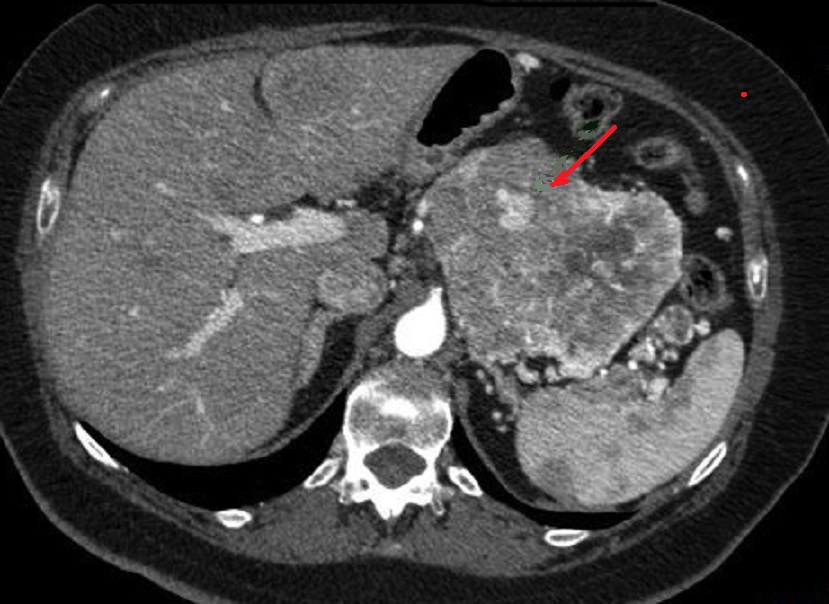

Les tumeurs endocrines

pancreas . Coupe TDM C+ |

Image radiologique

d'un tumeur endocrine non fontionelle du queue

pancreas a grand taille . Ce que entraine une

deformation neoplasique du systeme veine splenique .

Image vde engainement veineuse et abrution

neoplasique de veine splenique ( fleche rouge c) |